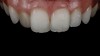

(9. through 11.) Preoperative esthetic case documentation using a smartphone and an EALS device.

One of the main advantages that smartphone cameras have over DSLR cameras is that nearly everyone is already very familiar with the technology; therefore, the incorporation of these devices into everyday practice does not require learning a new and unfamiliar skill set. The task of producing a series of high-quality clinical photographs for routine examinations (Figure 8), esthetic treatment planning (Figure 9 through Figure 11), or specialty care (Figure 12 and Figure 13) can be delegated with confidence to any staff member during the patient's initial office visit and will generally require less than 5 minutes of time to complete. When a DSLR camera is used, evaluation of the intraoral images either takes place on the small viewfinder built into the camera or necessitates the physical removal of the memory card from the camera to downloaded the images onto a computer for review. An added bonus of smartphone dental photography is that the phone's screen now replaces the much smaller viewfinder of a DSLR camera and provides the clinician with the ability to view and zoom into the patient images on a 5- to 6-inch, high-definition display.